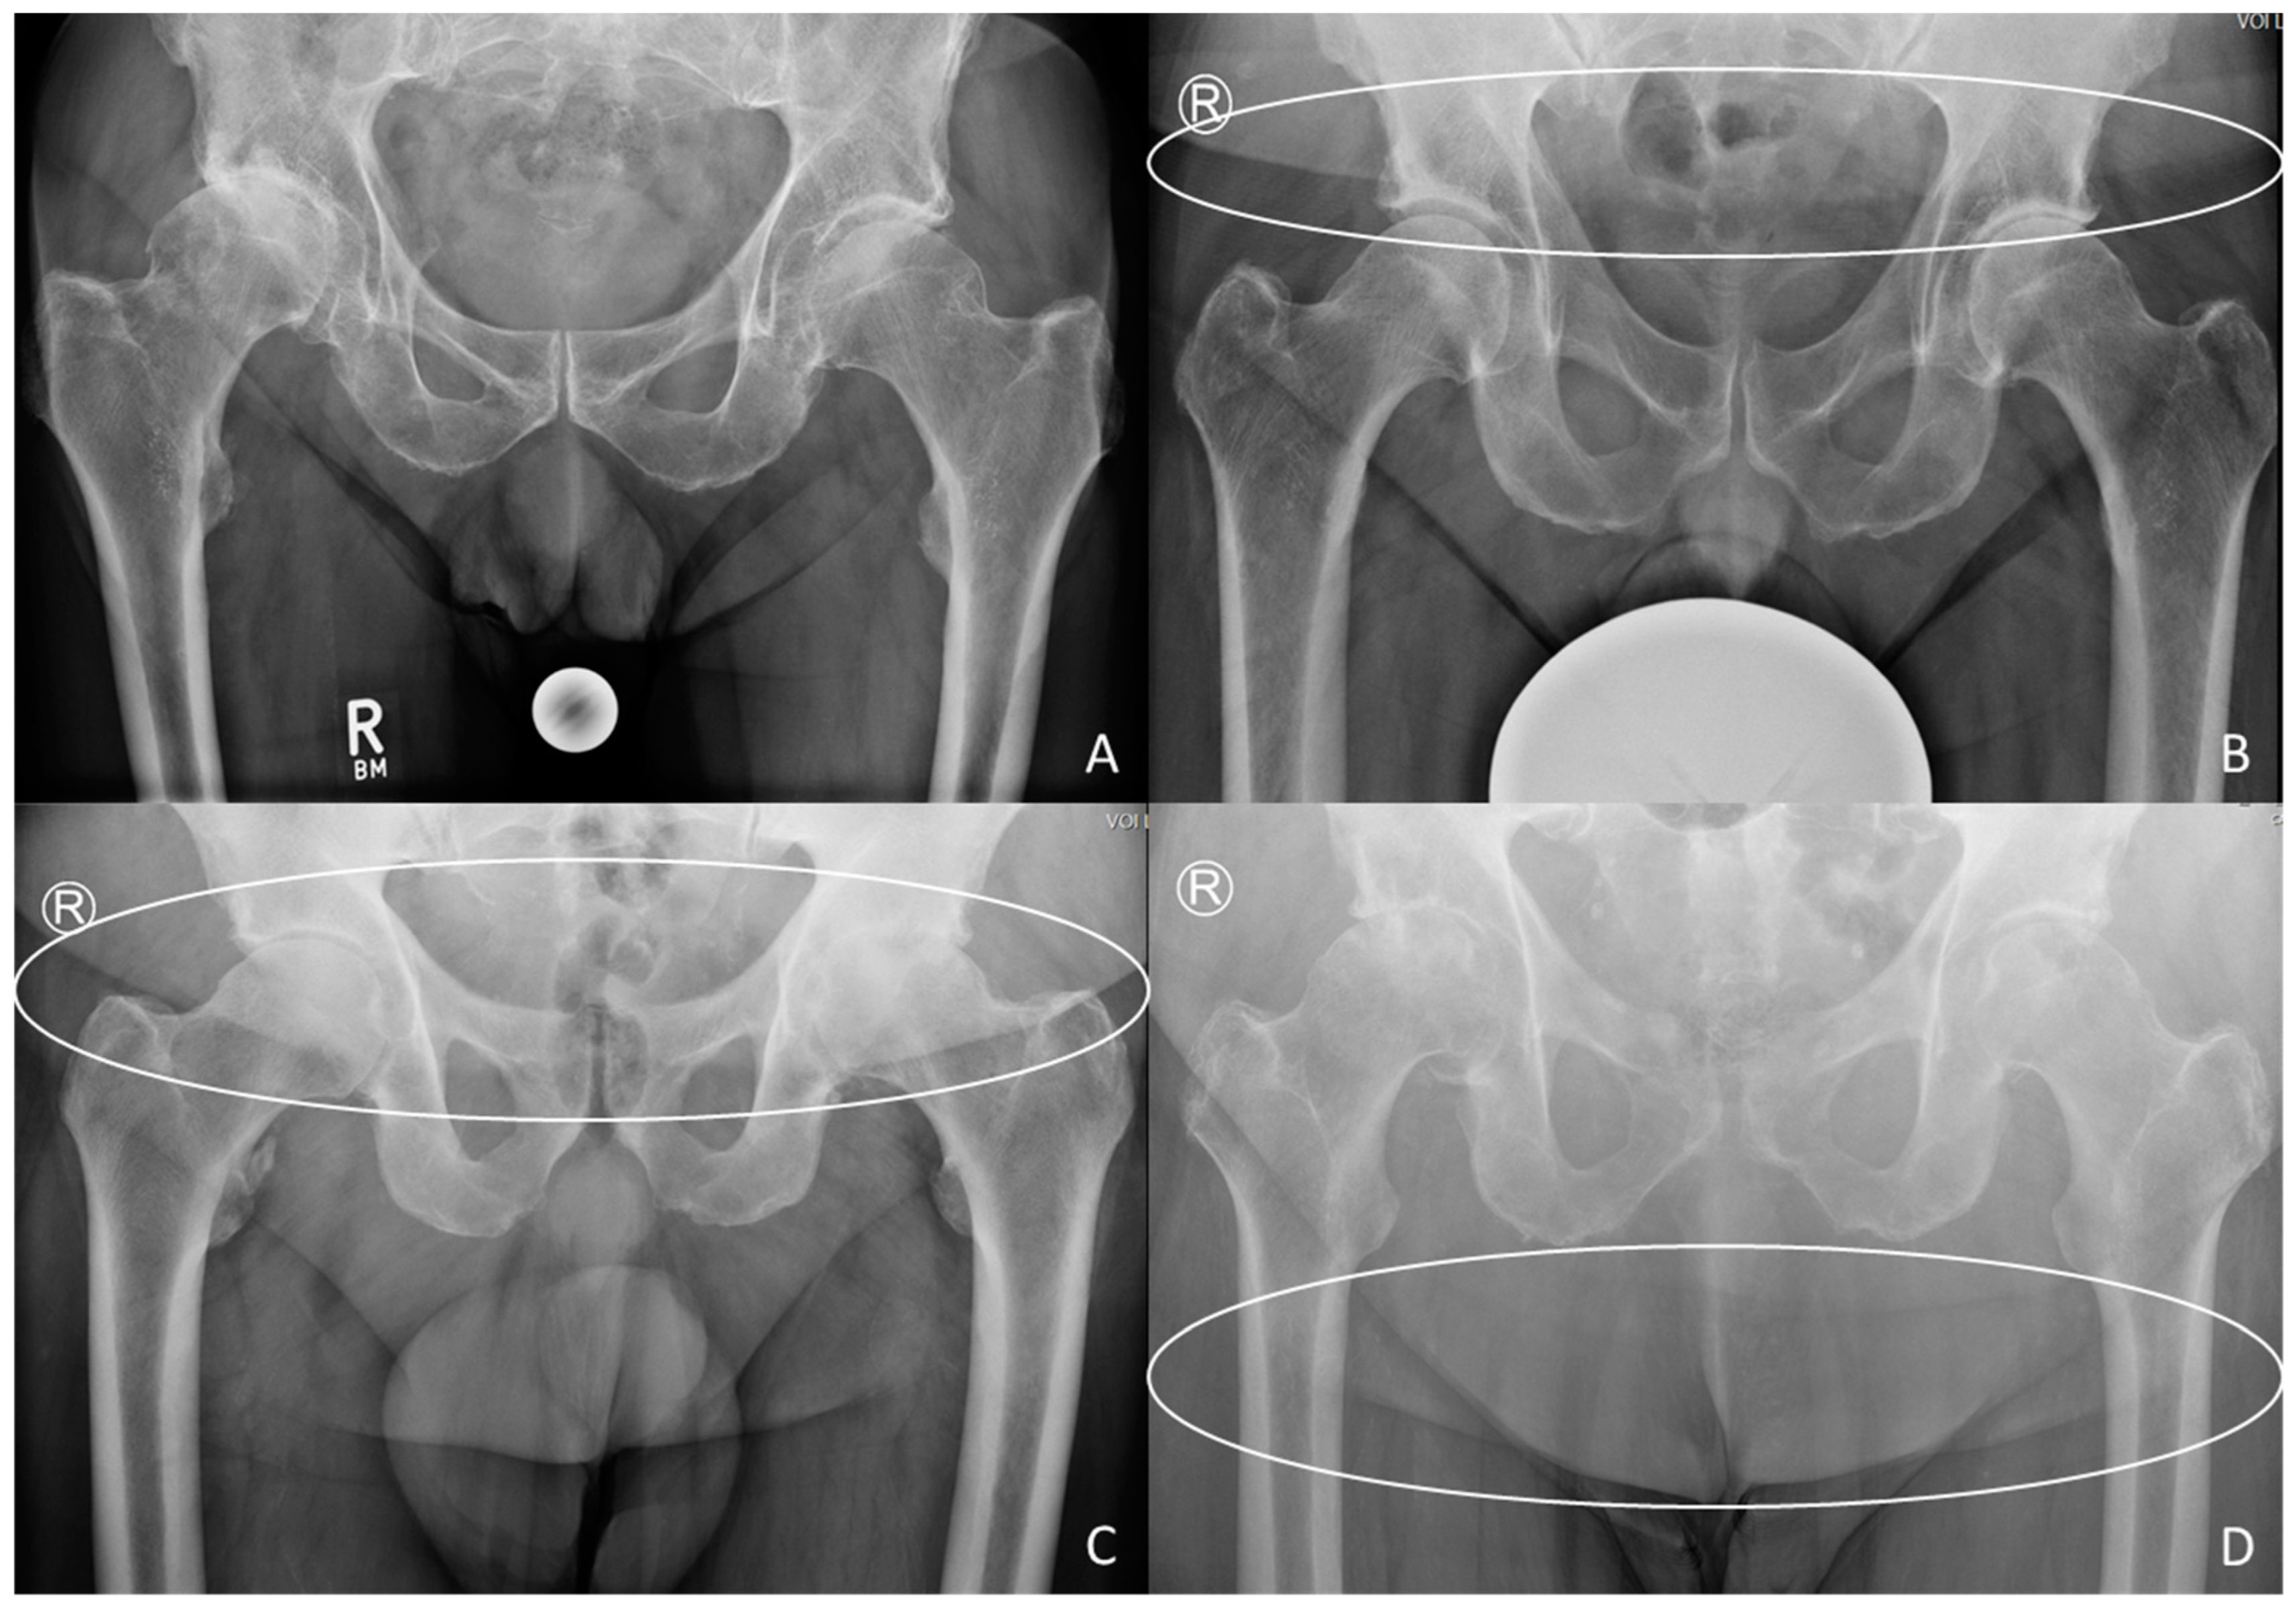

2.3. X-ray Grading